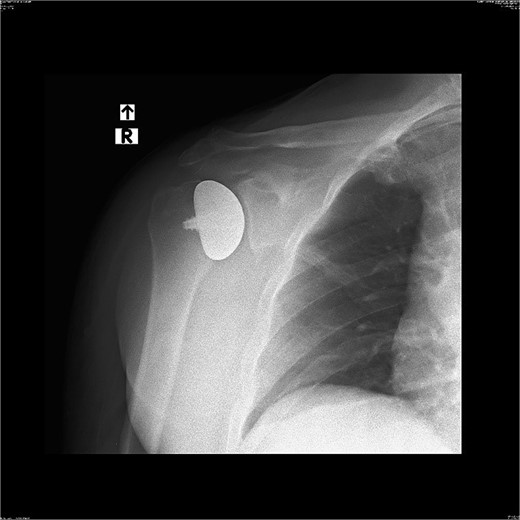

The peri and postoperative period passed without any complications. On day one after surgery, an X-ray image was taken (Fig. 9). The patient in good general and local condition was discharged from the hospital with a set of recommendations for rehabilitation. A sling was used to relieve the operated limb.

Rehabilitation was carried out from the day of the surgery and lasted for 16 weeks.

As a result, almost the full range of motion with a significant improvement in muscle strength of the right shoulder joint was achieved without any relevant pain reported by the patient. The results were confirmed by another right shoulder X-ray image (Fig. 10). The patient has been instructed to resume his pre-injury regular activities, including lifting heavy objects.